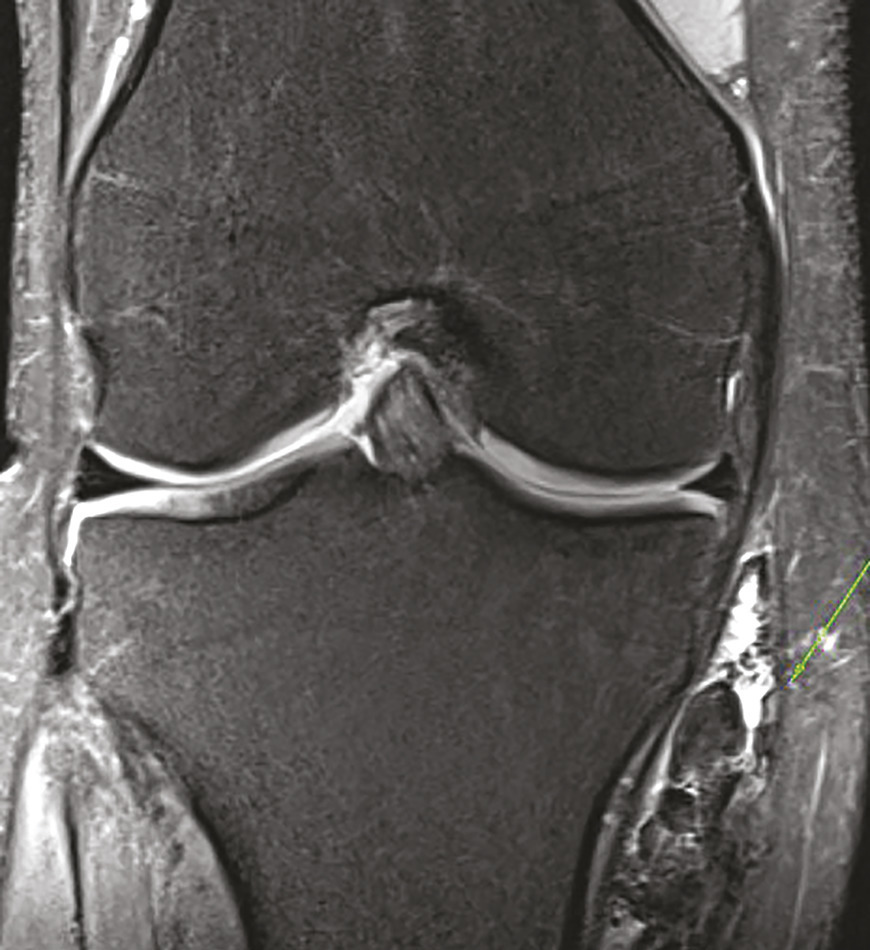

Ce jeune homme de 20 ans consultait pour une douleur du genou évoluant depuis 1 an initialement étiquetée bursite. Un traitement médical lui avait été prescrit pour cette affection. Devant la persistance de la douleur, une échographie était réalisée qui montrait une formation kystique atypique car mal limitée, à paroi épaissie et hyperhémique. Le caractère particulier de cette lésion amenait à prescrire une imagerie par résonance magnétique (IRM) qui montrait une infiltration évoquant une synovite villonodulaire en regard de l’insertion des muscles de la patte d’oie (fig. 1 et 2 ). La lésion était réséquée chirurgicalement et l’examen anatomopathologique notait une prolifération de cellules mononucléées ovoïdes ou comportant des inflexions fusiformes, associées à des histiocytes spumeux et du pigment hémosidérinique, sans atypie cytononucléaire ni activité mitotique, confirmant le diagnostic.

La synovite villonodulaire est une affection articulaire rare, focale ou diffuse, caractérisée par une hyperplasie villeuse ou nodulaire de la synoviale touchant principalement le genou et la hanche ; son étiopathogénie reste discutée. L’histoire naturelle de la forme diffuse, son caractère agressif ainsi qu’une composante génétique lui confèrent un aspect pseudotumoral qui la différencie de la forme locale. La symptomatologie est peu spécifique et entraîne un retard diagnostique. L’IRM fait le diagnostic (à condition d’y penser et de le préciser au radiologue). Le traitement de la forme focale est simple, son pronostic très bon, avec un taux de récidive faible. La forme diffuse impose une prise en charge plus radicale avec un taux de récidive élevé.1 Un traitement adjuvant ainsi qu’une surveillance sur le long terme sont recommandés. Des données récentes montrent l’intérêt de nouveaux traitements par immunothérapie, dont les modalités pratiques sont encore discutées.2